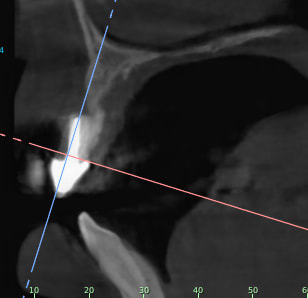

Je rajoutes quelques coupes et une rétro... C'est vraiment un massacre à la tronçonneuse!

C1 yphslc - Eugenol

C2 zxqv4g - Eugenol

C3 eyq9c9 - Eugenol

C4 nbfjjy - Eugenol

C5 tbh27p - Eugenol

C6 hpnjso - Eugenol

C7 wstgml - Eugenol

C8 zrgdkv - Eugenol

C9 l71h8s - Eugenol

C10 llgubu - Eugenol

C11 xl426v - Eugenol

24/04/2019 à 15h19

D'autres coupes et une rétro

2 ozhekl - Eugenol

3 r9cfdm - Eugenol

1 skjekn - Eugenol

Rétro24042019 sngvhg - Eugenol